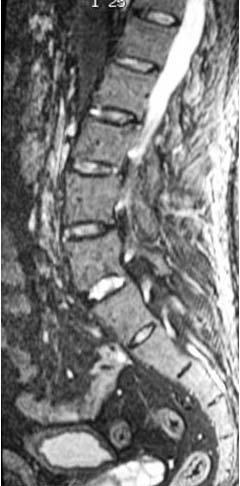

Dos pacientes presentaron afectación de elementos posteriores vertebrales, hecho no contemplado en la puntuación ASspiMRIa. En nuestro estudio, dichos pacientes son considerados, tal y como indica dicho sistema de puntuación, como puntuación 0 (normal). Así mismo, existió afectación discal en tres pacientes (tabla 2) (fig. 5).

Fig. 5.—SE T1 con supresión grasa y contraste paramagnético.Hiperintensidad discal L5-S1.